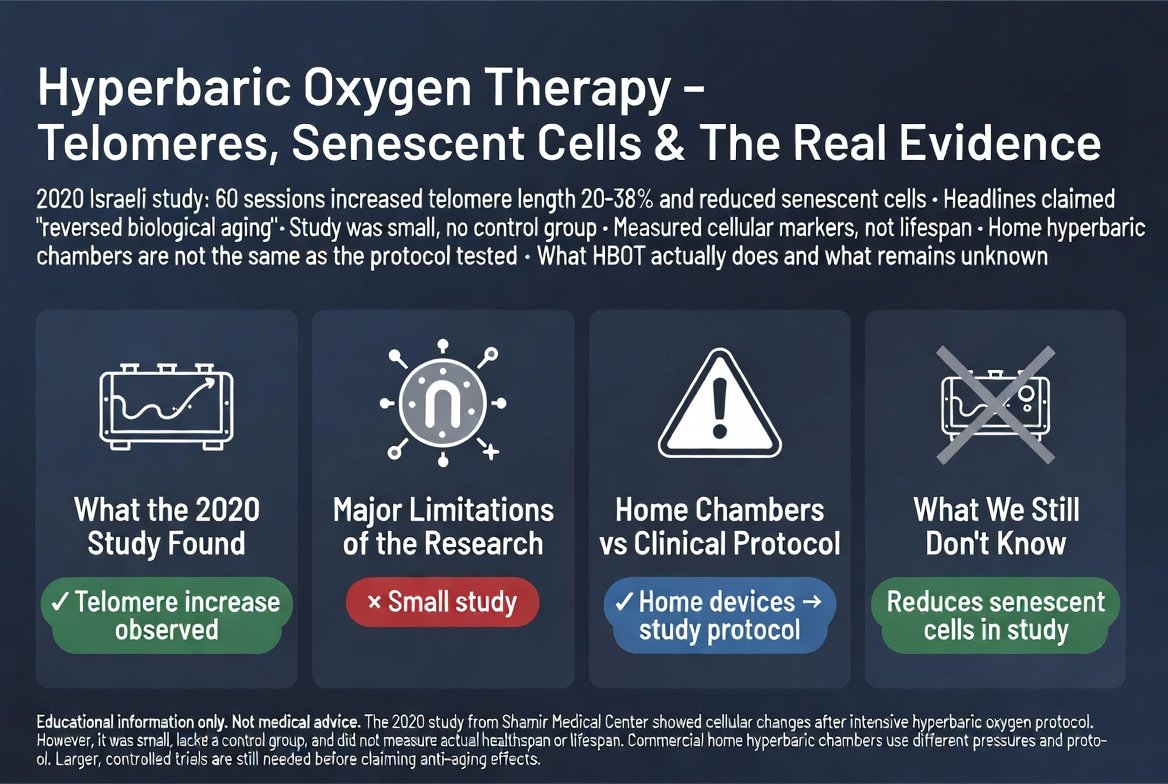

ב-2020 פרסם צוות ישראלי מהמרכז הרפואי שמיר ומאוניברסיטת תל אביב מחקר שעורר סערה: 60 טיפולים בתאי לחץ עם חמצן היפרברי האריכו את הטלומרים בתאי הדם ב-20%...